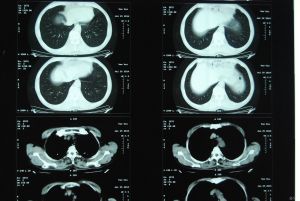

1、粗濕羅音:又稱大水泡音。發生於氣管、支氣管或空洞部位,多出現在吸氣相早期。昏迷或瀕死的患者因無力排出呼吸道分泌物,於氣管處可聽及粗濕羅音,有時不用聽診器亦可聽到,謂之痰鳴。

3、細濕羅音:又稱小水泡音。發生於小支氣管,多在吸氣後期出現。常見於細支氣管炎、支氣管肺炎、肺淤血和肺梗塞等。